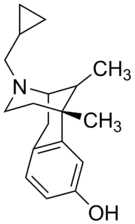

There are a number of broad classes of opioids:[260]

Benzomorphan derivatives

- Dezocine—agonist/antagonist

- Pentazocine—agonist/antagonist

- Phenazocine